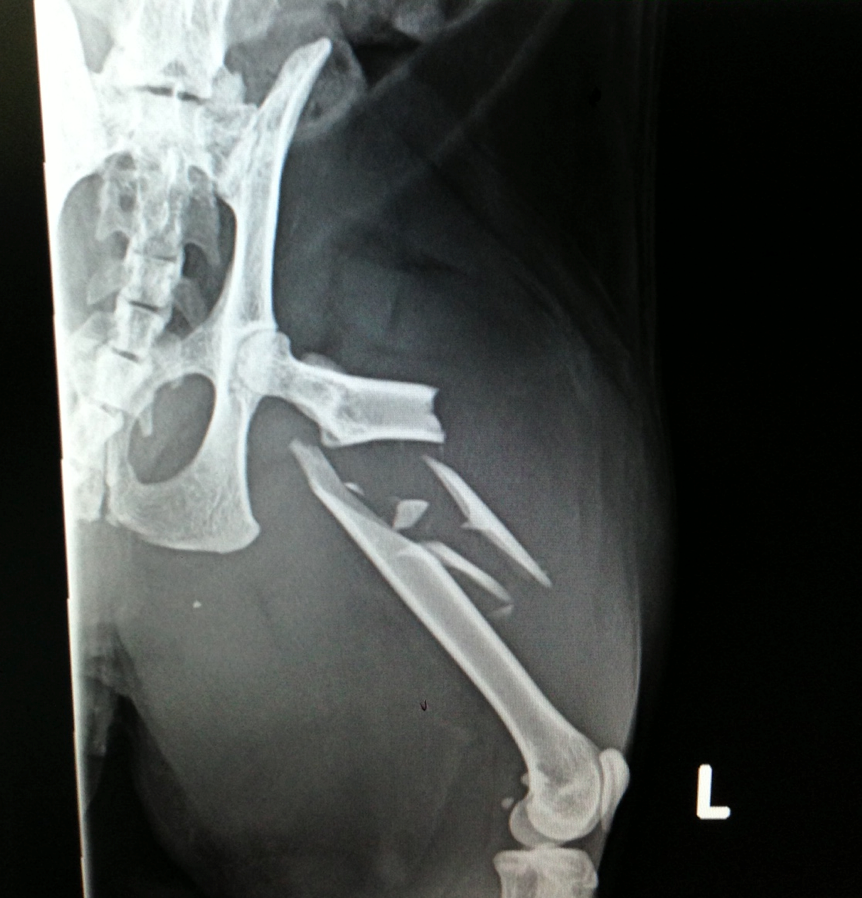

Geoffrey is a 7 year old Himalayan cross who went missing for 5 days, and when he eventually returned, had suffered a severe fracture to his femur in his left hind leg. The image below shows the severity of the break.

Geoffreys femur had shattered into several pieces

Geoffrey had suffered a comminuted fracture (a fracture where the bone has broken into several pieces) and had a lot of overriding (bone that has slipped out of its usual position) due to the break being 5 days old when he was presented to one of our hospitals. He was going to need surgery to repair it.